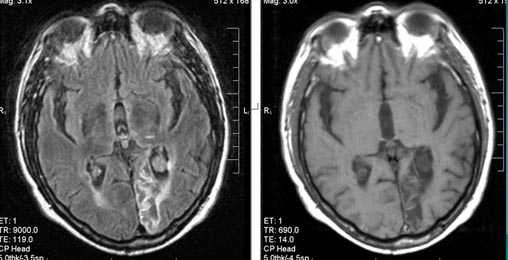

Характерным проявлением ДЭП на МР-томограммах является наличие множественных очагов глиоза.

В белом веществе левой лобной и обеих теменных долей, преимущественно субкортикально, выявлены множественные мелкие очаги хронической ишемии (большинство локализованных в бассейне правой средней мозговой артерии).

Проявлением хронической ишемии является также развитие выраженных дистрофических изменений белого вещества паравентрикулярной локализации - лейкоареоз.

Выраженные дистрофические изменения белого вещества паравентрикулярной локализации - лейкоареоз.

Сочетание мультифокальных очаговых изменений с диффузной кортикальной церебральной атрофией.